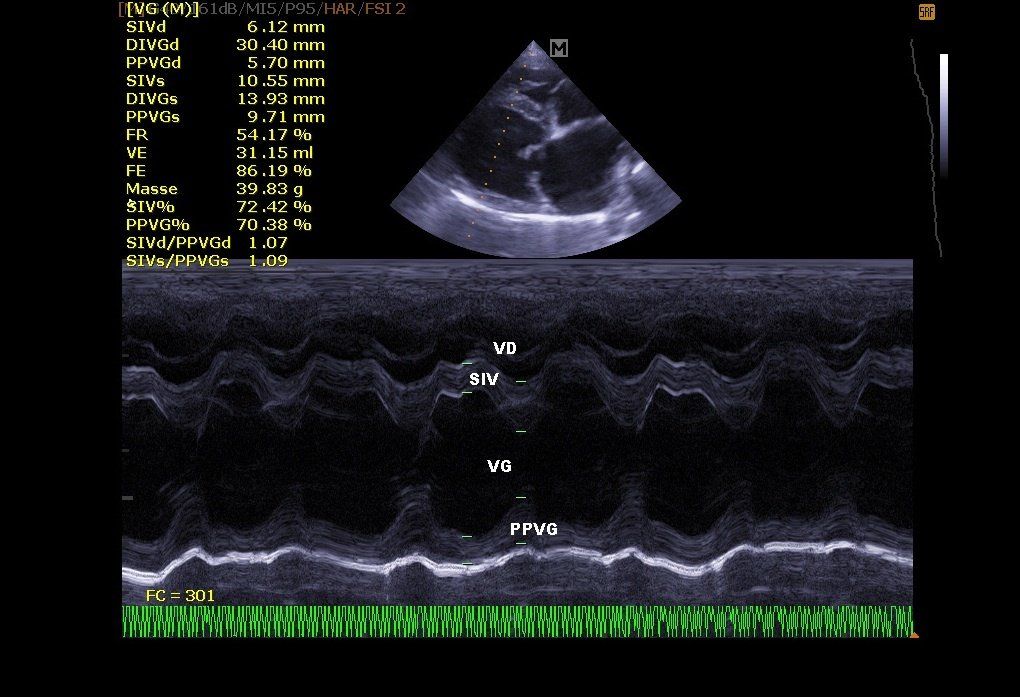

Échographie cardiaque:

Elle permet de visualiser les différentes parties du cœur (parois, cavités, valvules) et de repérer d’éventuelles anomalies qui empêchent un fonctionnement cardiaque correct . En cas d’insuffisance cardiaque, l’échocardiographie permet aussi un suivi régulier de la morphologie cardiaque. Il est alors plus facile de réajuster le traitement mis en place.